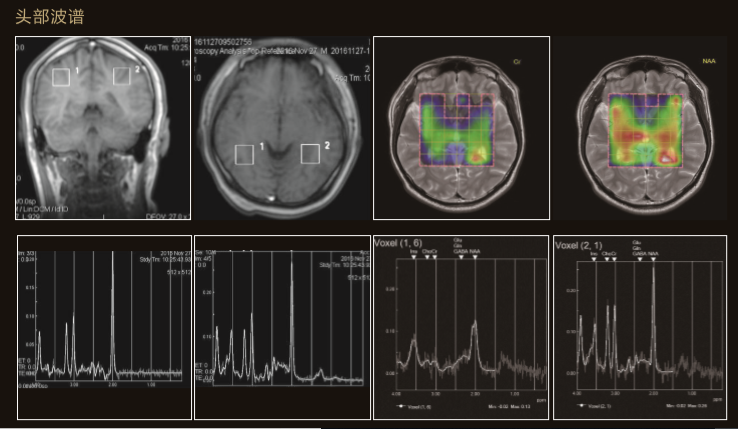

Apsaras飛天不僅采用極高均勻度的磁體系統,還配備了高階勻場系統可大範圍的高階磁場校正,以獲得具有臨床價值的圖像。

Apsaras飛天在保持以往使用便捷的前提下,應用程序支持更全面的臨床應用和發展。